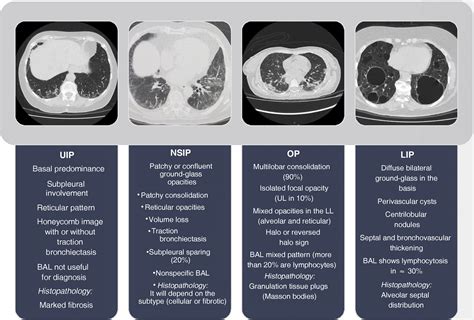

Diagnosing NSIP typically involves a combination of clinical evaluation, imaging studies, and sometimes a lung biopsy. High-resolution computed tomography (HRCT) scans of the chest can reveal characteristic patterns of lung injury, such as ground-glass opacities and reticular markings. However, these findings may overlap with other ILDs, making it challenging to distinguish NSIP based on imaging alone. A lung biopsy may be necessary to confirm the diagnosis and differentiate NSIP from other conditions, such as usual interstitial pneumonia (UIP) or organizing pneumonia (OP). The biopsy sample is examined under a microscope to assess the pattern of lung injury and identify any specific features that are characteristic of NSIP. Once the diagnosis is confirmed, treatment options may include corticosteroids, immunosuppressant medications, and pulmonary rehabilitation to improve lung function and quality of life.